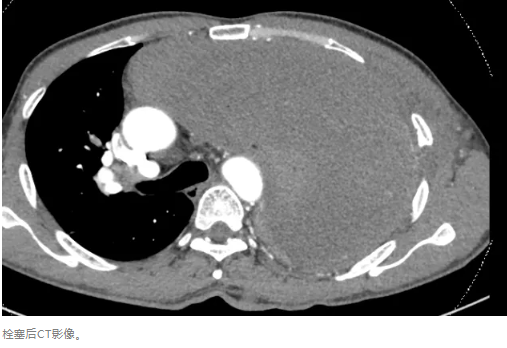

4、最后也是最重要的,于2024年9月14日在介入科主导下行肿瘤相关滋养血管栓塞治疗,治疗后复查胸部增强CT对比,见肿瘤血运明显减少。